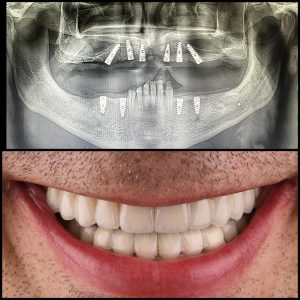

Implanti

Dentalni implantati predstavljaju efikasno rešenje za nadoknadu zuba. Vraćaju funkcionalnost, estetski izgled i sposobnost pravilnog govora